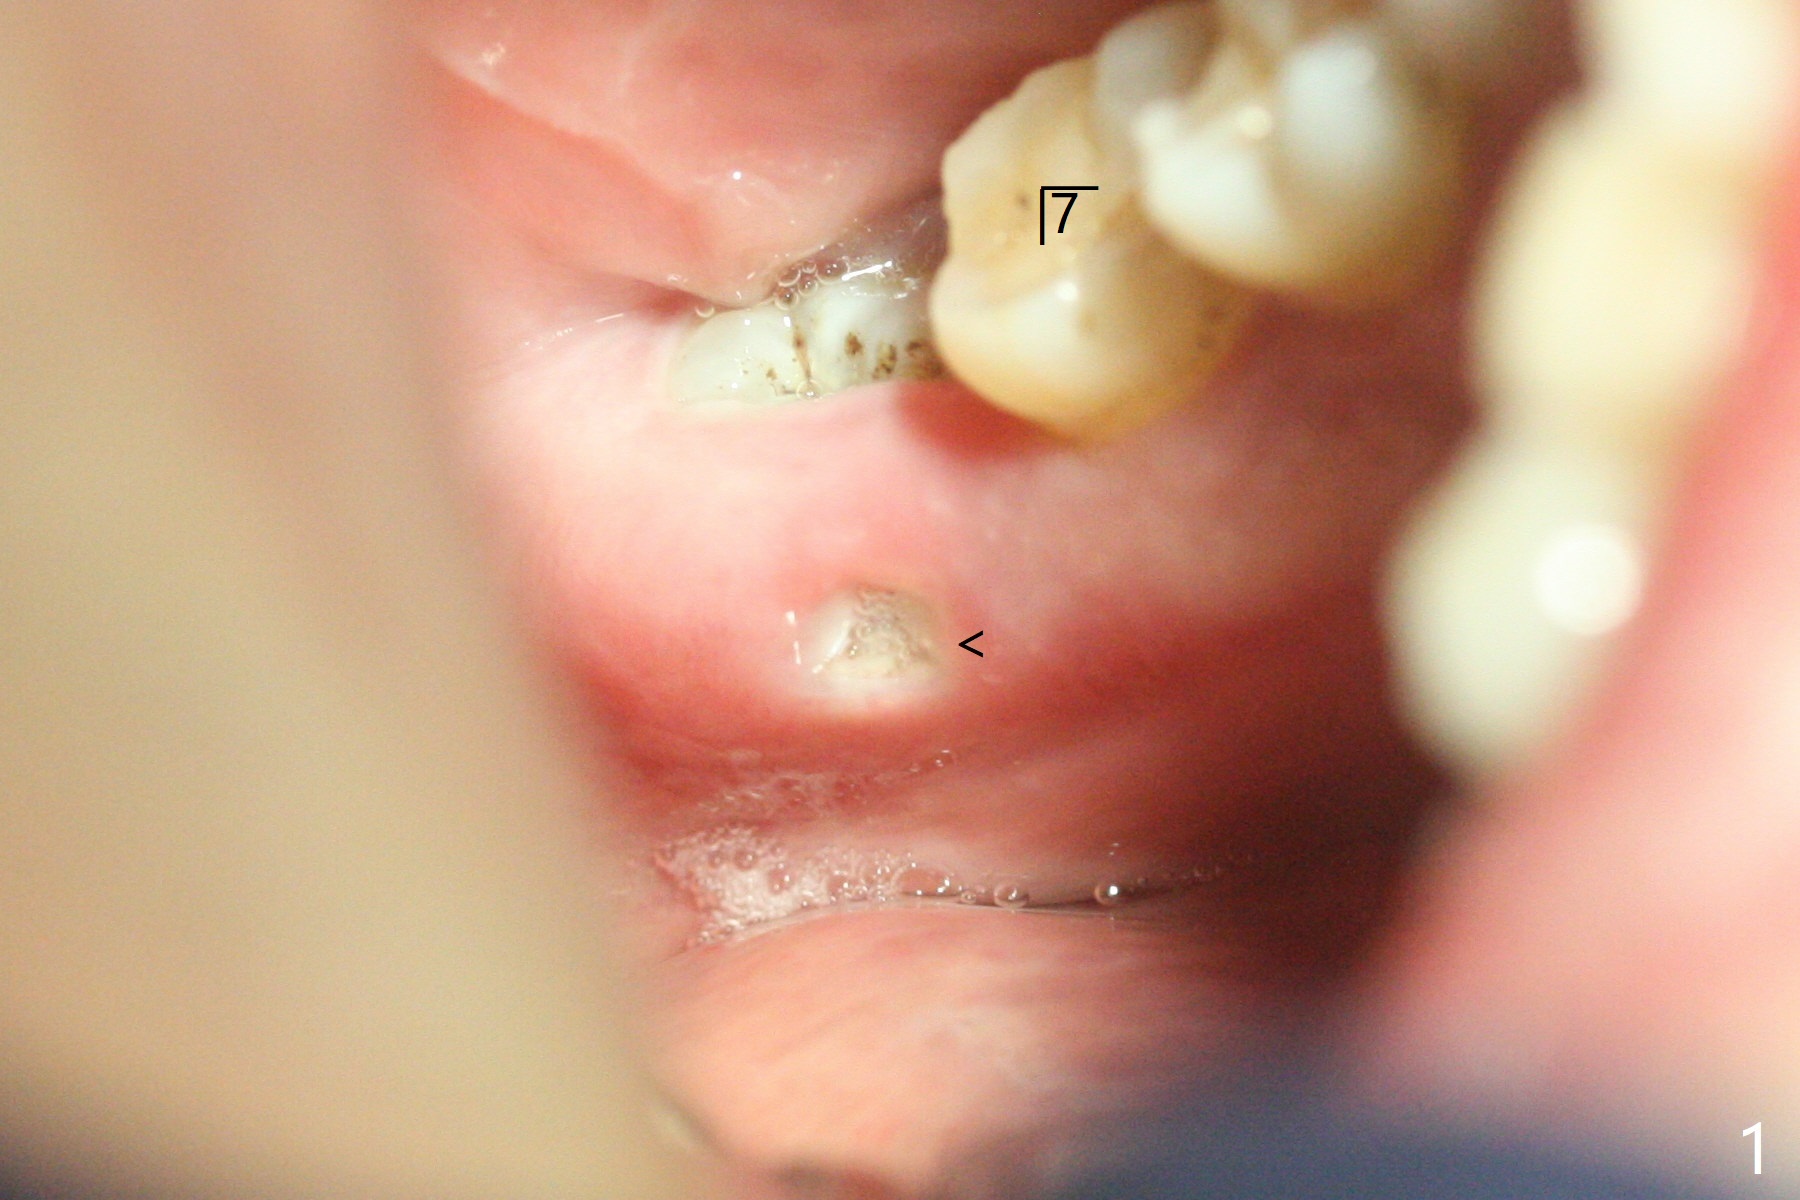

65岁女,南方人(广州),主诉左下肿胀,8舌侧粘膜穿孔(图一(舌侧观):<),初步问诊,回答:“全身没问题”,详细问诊:骨质疏松,静脉注射Reclast两年,准备拔除使用PRF修复缺损,全景片显示7远中骨质吸收严重(图二),因此8拔出后,牙槽窝塞入胶原塞(图五:C),将粘性骨粉放置7近中,远中(图五:白*)以及颊侧(黑*),把一片PRF膜覆盖骨粉(7颊侧,8牙槽窝口),另外一片放置于8舌侧穿孔(图四:箭头)颊侧,促进愈合,然后使用4-0 PGA缝合(图三(颊侧观),图四(舌侧观))。术后5天用钢丝(图六:*)和树脂固定松动牙,并且降低咬合。舌侧穿孔正在愈合(图七:>)。虽然术后三周智齿伤口裂开,但是没有症状,病人满意第二磨牙不再松动(图八),开始深洗。下次复诊拍摄根尖片观察骨质愈合。术后二个月第二磨牙远中没有骨质再生(图九),临床上远中牙根暴露。